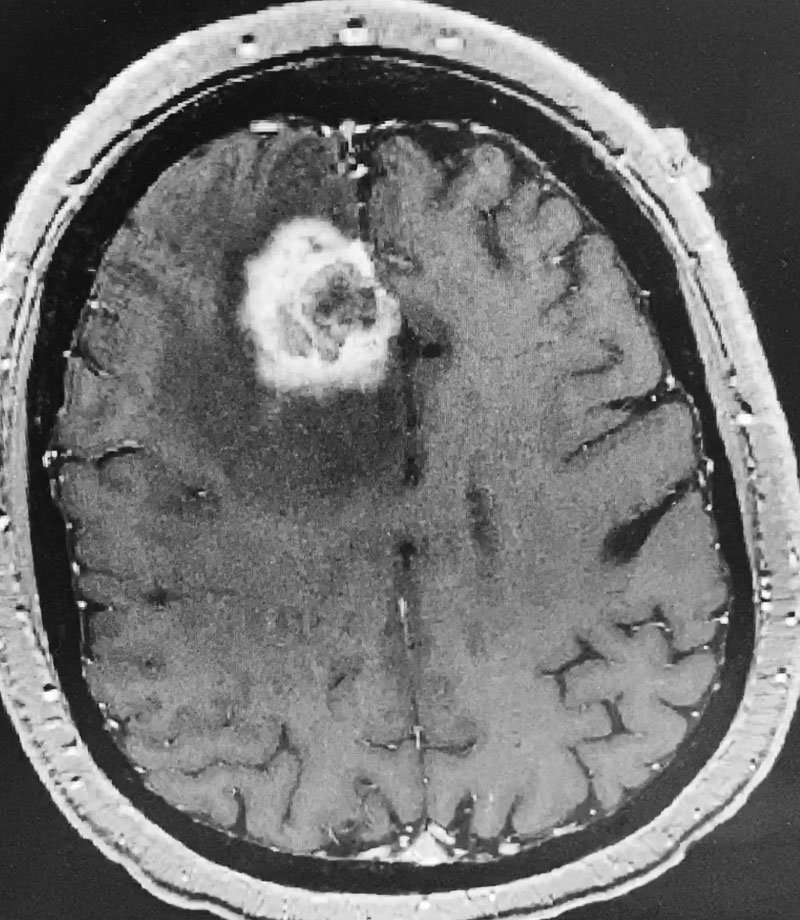

Figure 1: Sagittal post-contrast MRI.

The patient subsequently had increased headaches and weakness. MRI showed the mass had increased further, with persistent surrounding edema (Figure 1). Systemic work-up showed no active metastatic disease. It was suspected that there was recurrence of metastatic tumor as well as some component of necrosis (Figure 2). The patient underwent a right frontal craniotomy, by Dr. Michael Brisman, with brainlab stereotactic guidance. A cortical incision was made right over the mass. The mass was consistent primarily with metastatic tumor. The tumor was surgically removed.